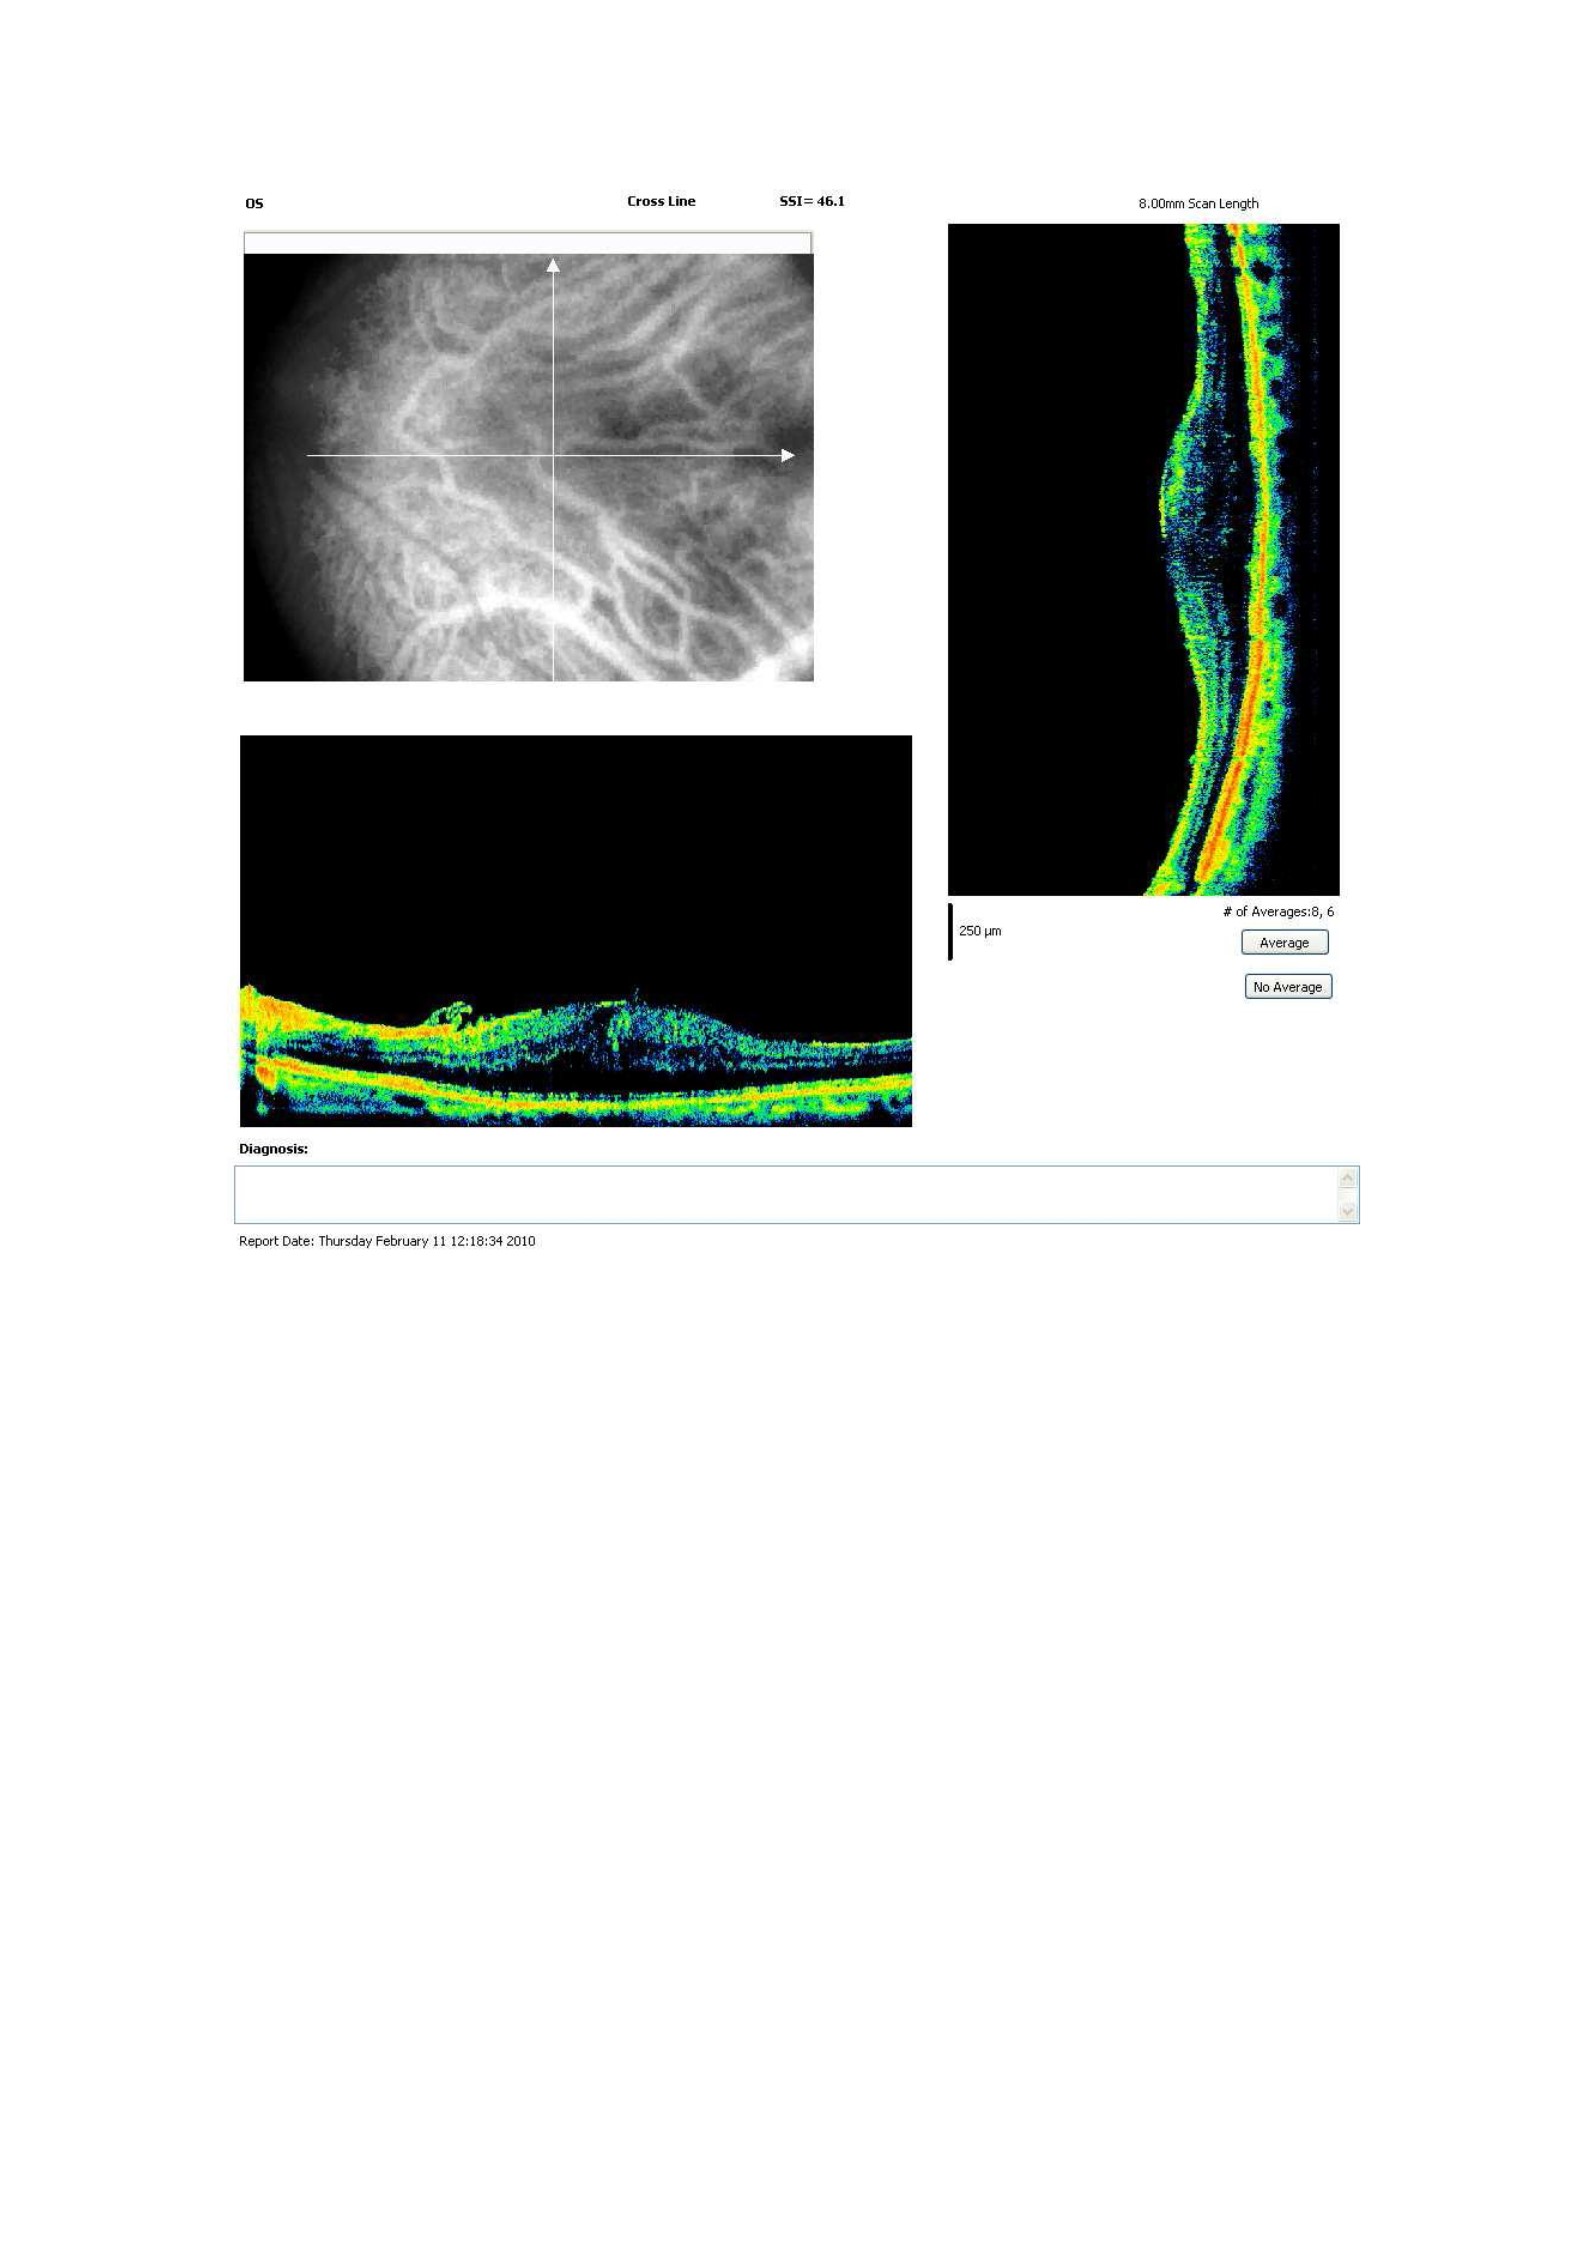

Esta es la conclusión del estudio realizado por el Dr Nathan R. Mathews y colaboradores (1) del departamento de Oftalmología del Medical College of Wisconsin. Estos investigadores evaluaron el contorno foveal de 41 ojos afectados de membrana epirretiniana (MER) idiopática sometidos a vitrectomía (pelado de membrana epirretiniana y de limitante interna) previo a la cirugía y en el postoperatorio (a los 4 meses). Buscaron si existía una correlación entre el contorno foveal antes de la cirugía y el contorno foveal postquirúrgico, el grosor de la retina y la ganancia de agudeza visual.

Encontraron que, de aquellos pacientes que habían perdido la depresión foveal preoperatoriamente, la mayoría no recuperaron la depresión foveal fisiológica en el postoperatorio, aunque el grosor retiniano disminuyó. Además, aquellos ojos que presentaban en el preoperatorio un mayor grosor en la fóvea que en la mácula circundante no experimentaron una ganancia visual, aunque también disminuyera el grosor retiniano.

Este es uno de los diversos estudios actuales que analizan la morfología de las MER en la OCT con el propósito de optimizar el momento en el que deben ser operadas para lograr el mejor resultado anatómico y funcional. Otros estudios se han centrado en la integridad de la capa de fotorreceptores.